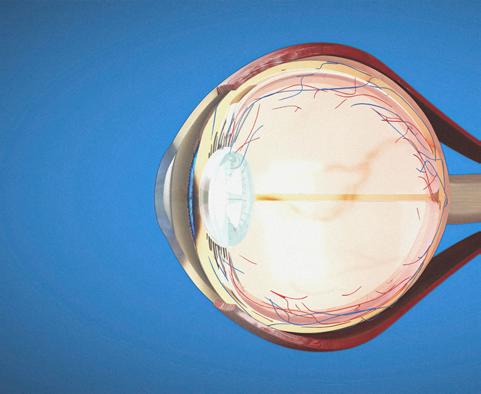

Poland’s first transplantation of artificial corneas of both eyes (Medical University of Silesia in Katowice)

Seeking new therapeutic options for the treatment of hereditary diseases of the retinae based on the analysis of protein interactions (Medical University of Silesia in Katowice)